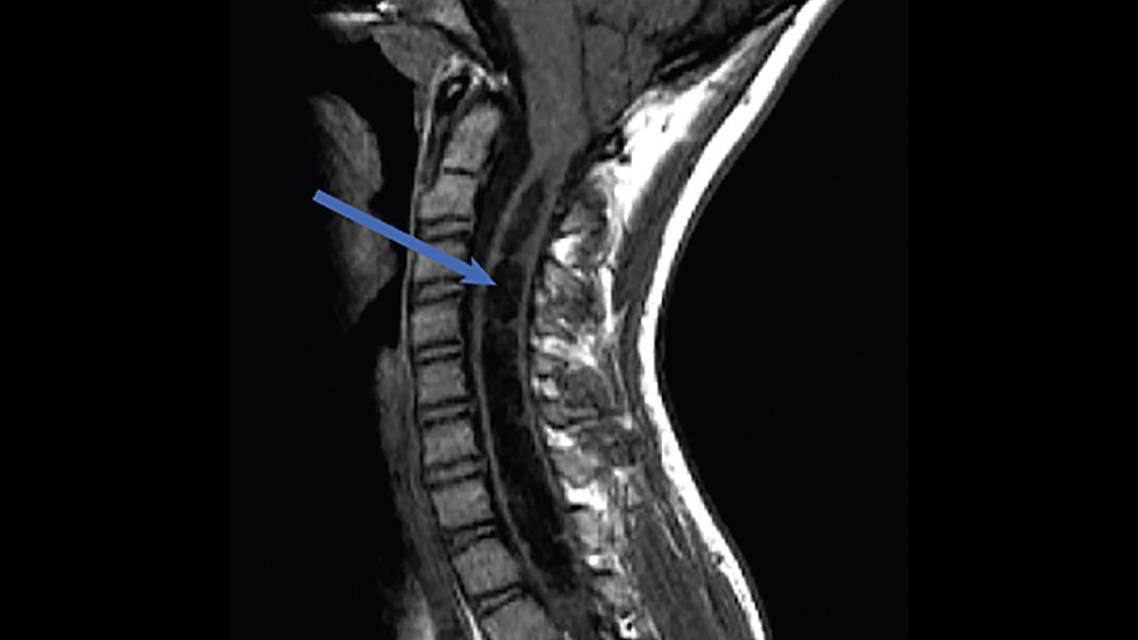

Syrinx

A syrinx is a slit-like cavity within the spinal cord (Figure 1). The classification of spinal cord syringes has been confusing with conflicting nomenclature. In 1 classification system, the term syringomyelia describes a syrinx within the parenchyma of the spinal cord, and hydromyelia describes a syrinx caused by dilation of the central canal. It has been suggested, however, that the term hydromyelia be discarded, and syringomyelia be classified into 5 groups: hydrocephalic, hindbrain-related, nonhindbrain-related, complex, and idiopathic.1 Another classification system, which is most commonly utilized divides spinal cord syringes into 3 separate groups as follows.2